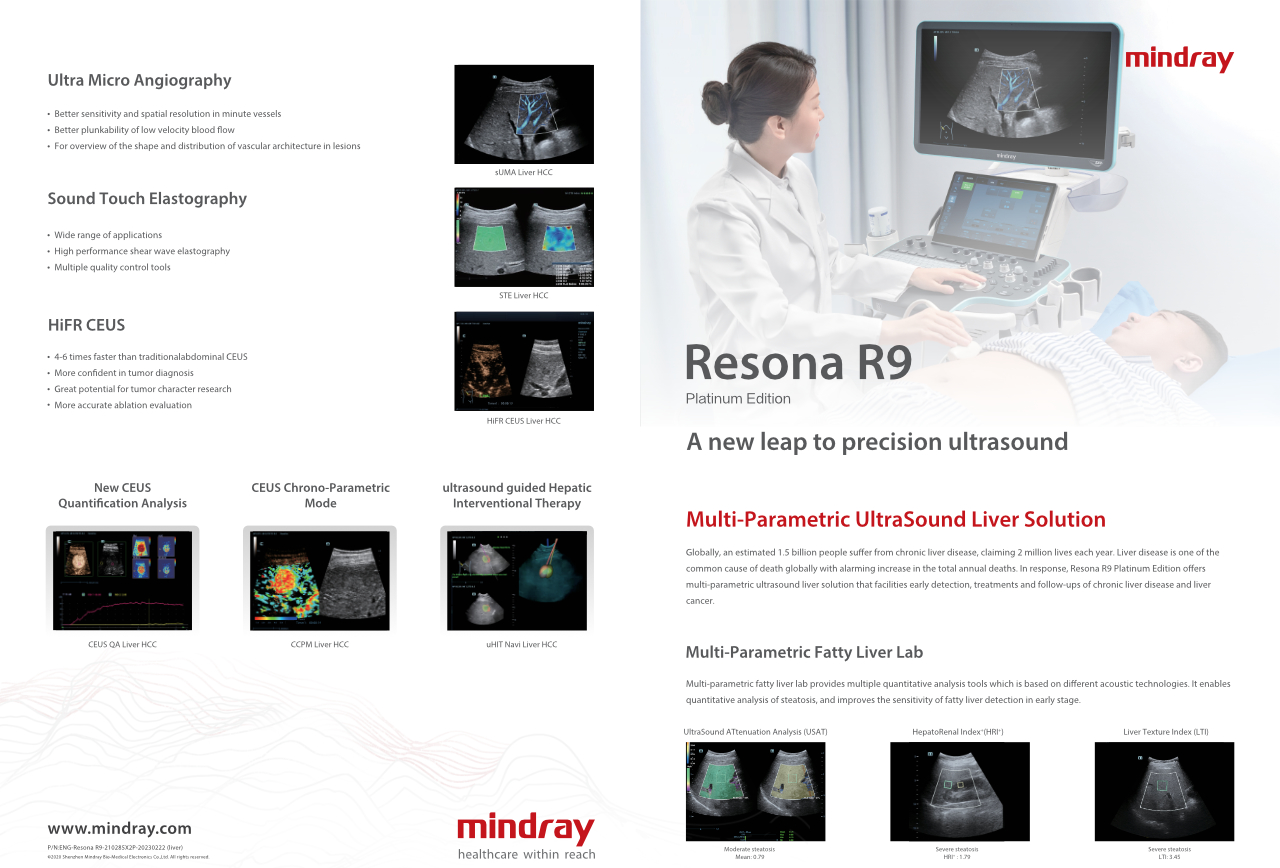

Comment voir le foie au mieux??

L'imagerie de contraste joue un r?le important en cas de lĂŠsions hĂŠpatiques focales, par exemple hĂŠmangiome ou cancer hĂŠpatique. La technologie d'imagerie de contraste UWN+ ultra-large et non linĂŠaire offre une meilleure pĂŠnĂŠtration, un rapport contraste-tissu plus ĂŠlevĂŠ, avec un index mĂŠcanique (IM) plus faible et une observation plus longue du temps de perfusion.